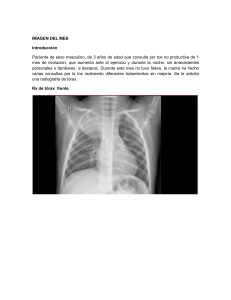

IMAGEN DEL MES Introducción Paciente de sexo masculino, de 3